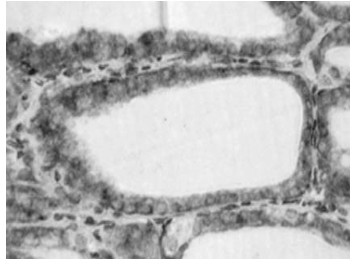

兔抗猪TPO多克隆抗体的制备与应用